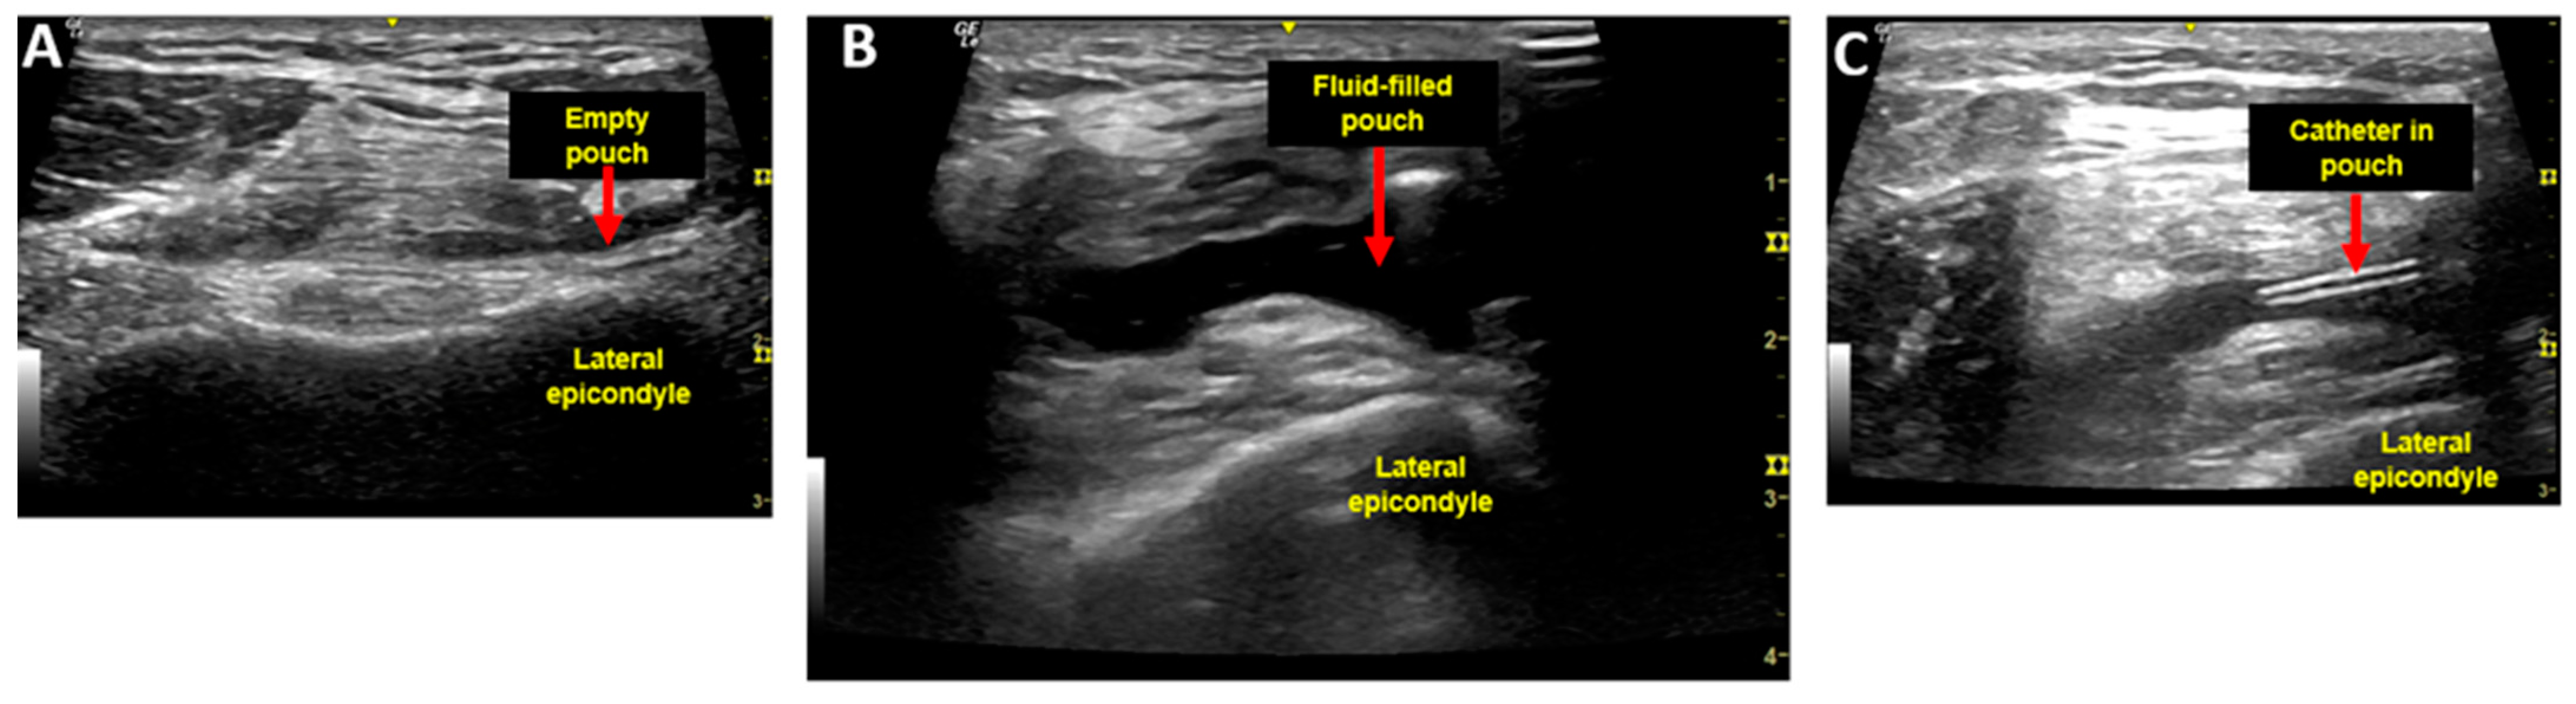

2.1. Injection Procedure and Injectate

2.2. Aspiration Procedure